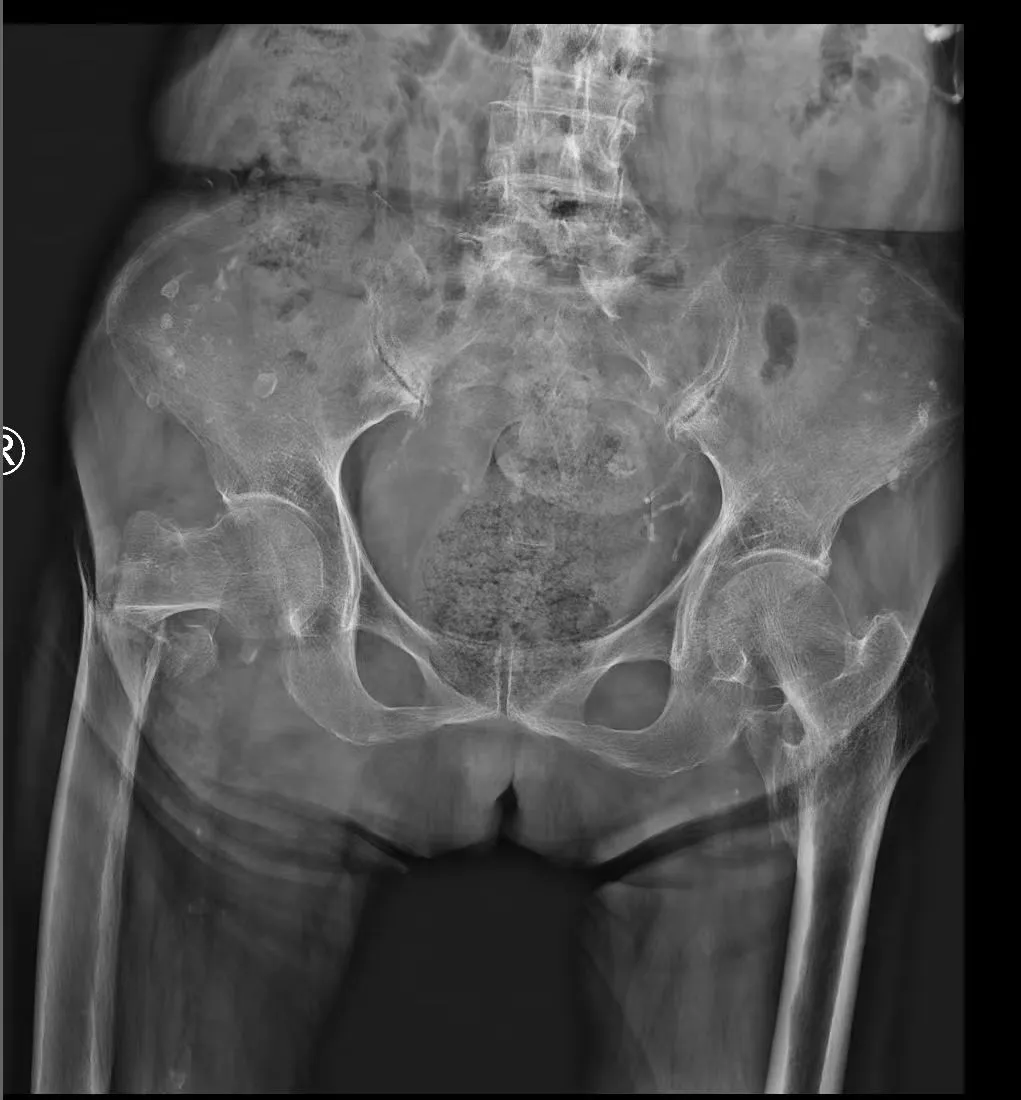

近日,一位101岁高龄的股骨粗隆间骨折患者,在西安市红会医院关节病院综合病区、心内科、麻醉科等多学科团队(MDT) 的精密协作与护航下,成功实施了直接前方入路(DAA)微创半髋关节置换术。此次手术突破了传统高龄骨折患者保守治疗的局限,不仅是一次技术上的成功,更是现代…